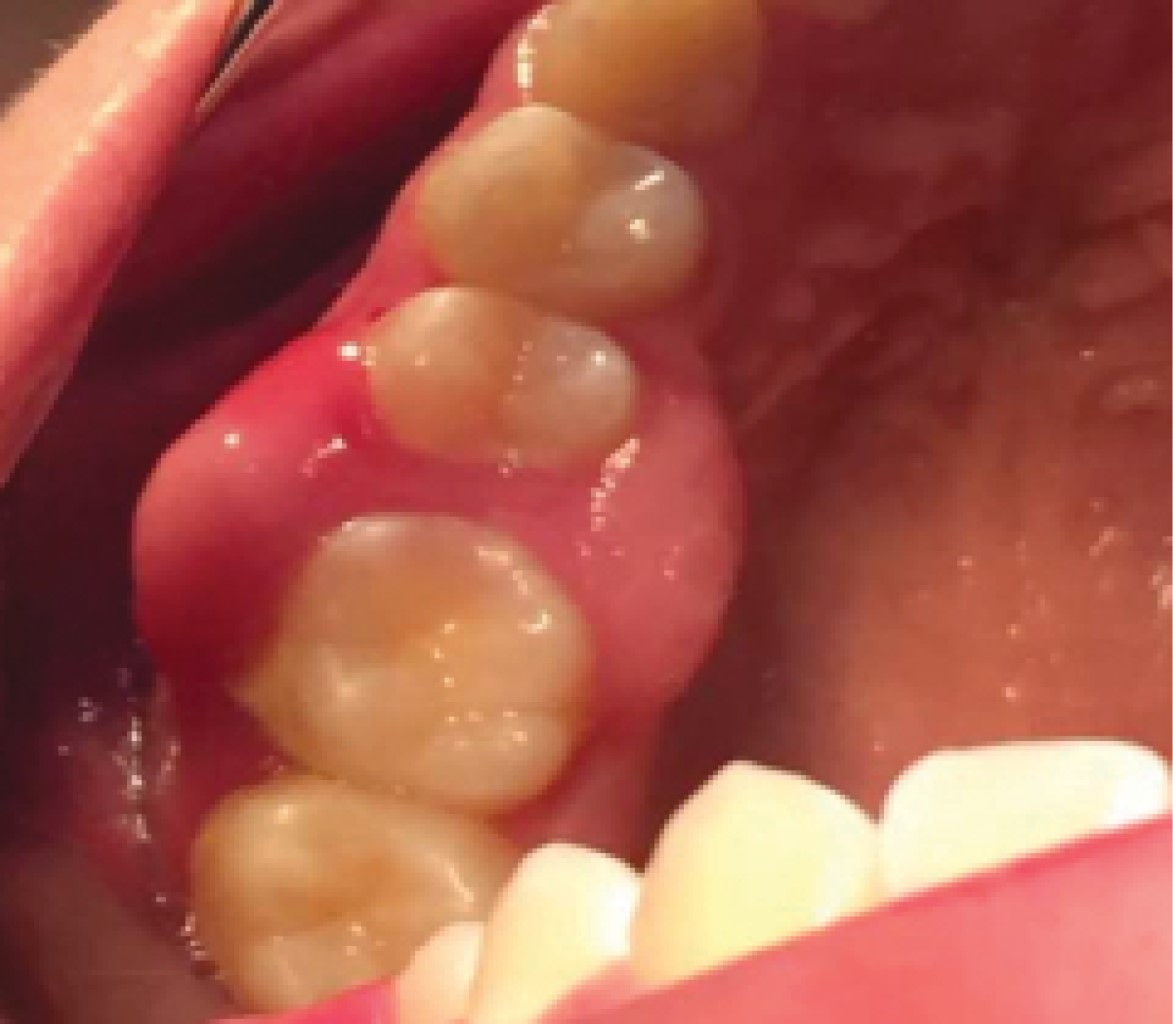

Figure 3